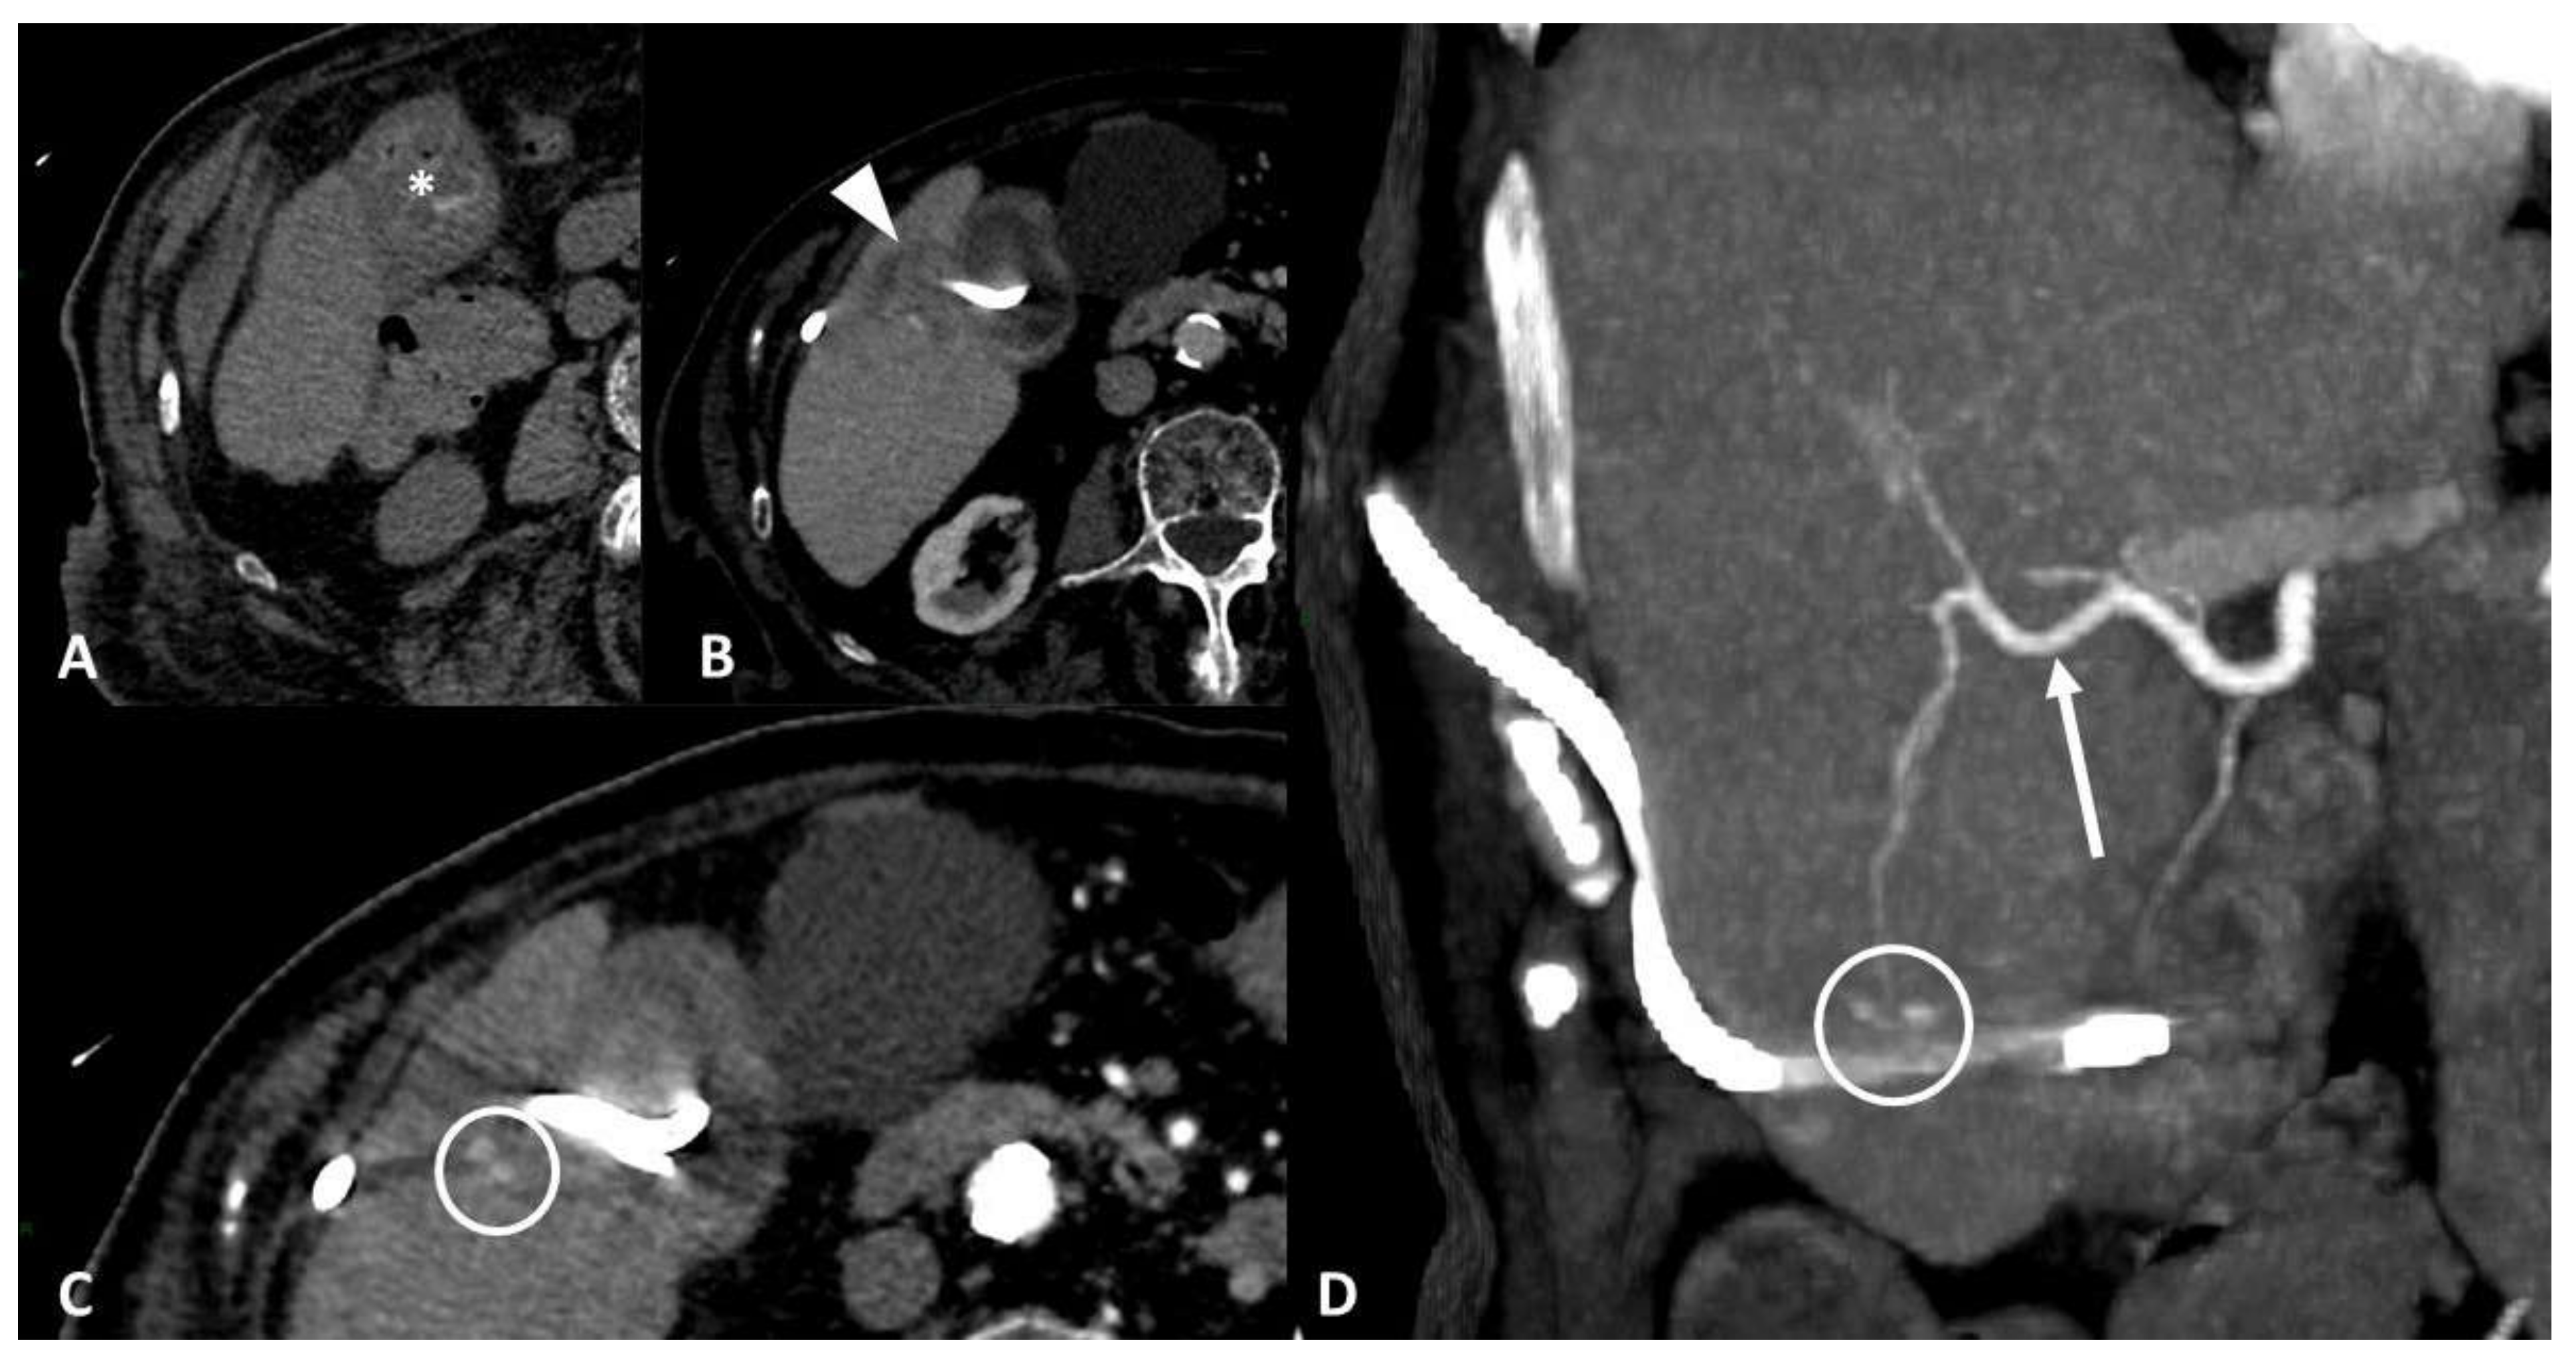

4.1. Vascular Injury

- Contegiacomo, A.; Amodeo, E.M.; Cina, A.; Distasi, C.; Iezzi, R.; Coppolino, D.; Attempati, N.; Manfredi, R. Renal artery embolization for iatrogenic renal vascular injuries management: 5 years’ experience. Br. J. Radiol. 2020, 93, 20190256. [Google Scholar] [CrossRef] [PubMed]